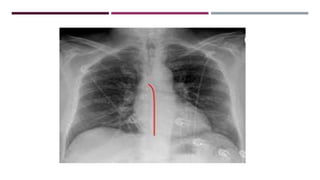

JUNCTION LINES

POSTERIOR JUNCTION LINE

ANTERIOR JUNCTION LINE

AZYGO-OESOPHAGEAL INTERFACE

PLEURO-OESOPHAGEAL STRIPE

PARASPINAL LINE